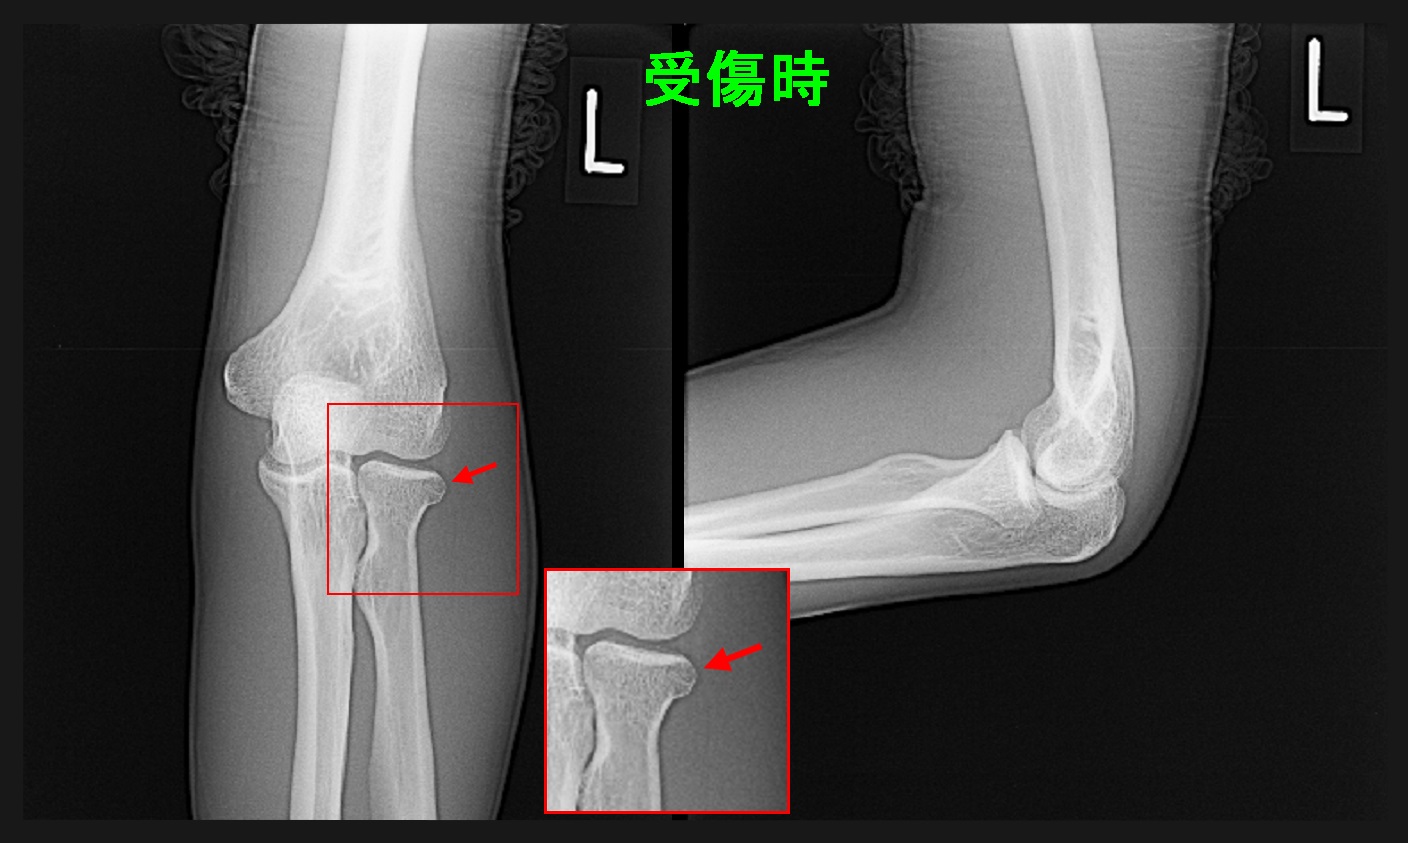

22才男 初診時Xp.jpg

レントゲン像では拡大部分の赤矢印部分が他部位に比して骨が少し黒っぽくなっている印象で、これが少し正常とはしがたい程度の印象です。受傷時はより異常は出にくいので、良くそれで骨折と診断できたなと不思議に感じる所見でした。